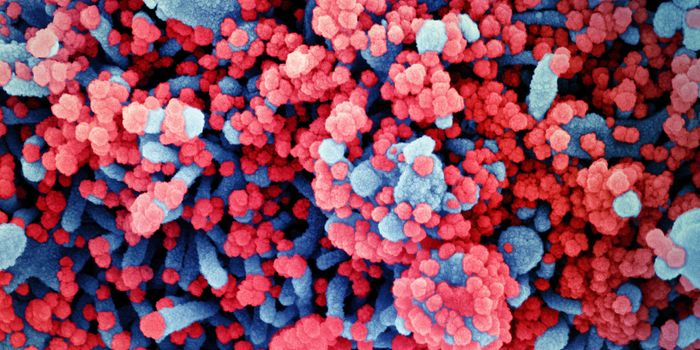

MAR 14, 2022ImmunologyThough it may happen at different rates for different microbes, mutations happen, and SARS-CoV-2, the virus that causes ...

FEB 08, 2022Clinical & Molecular DXViral experts are still unsure where and how the Omicron variant originated, but one thing is clear: it has overt ...

DEC 19, 2021MicrobiologyCOVID-19 may cause a wide range of symptoms that can impact many organs, but for those hospitalized with the disease, re ...

DEC 06, 2021MicrobiologySino Biological Newly Launched A Panel of Research Reagents for SARS-CoV-2 Omicron Variant (B.1.1.529) Beijing, China, D ...

NOV 26, 2021MicrobiologyOn Thursday, November 2021, South African health officials announced that they had identified a new variant of the pande ...

NOV 01, 2021Cell & Molecular BiologyResearchers have learned a lot about the SARS-CoV-2 virus since the start of the COVID-19 pandemic. We know that he viru ...

AUG 26, 2021MicrobiologyScientists have used a mouse model to visualize the progression of a SARS-CoV-2 infection as it led to sometimes fatal c ...

MAY 10, 2021MicrobiologyThe pandemic virus SARS-CoV-2 has changed the world in devastating ways, taking hundreds of thousands of lives & new var ...